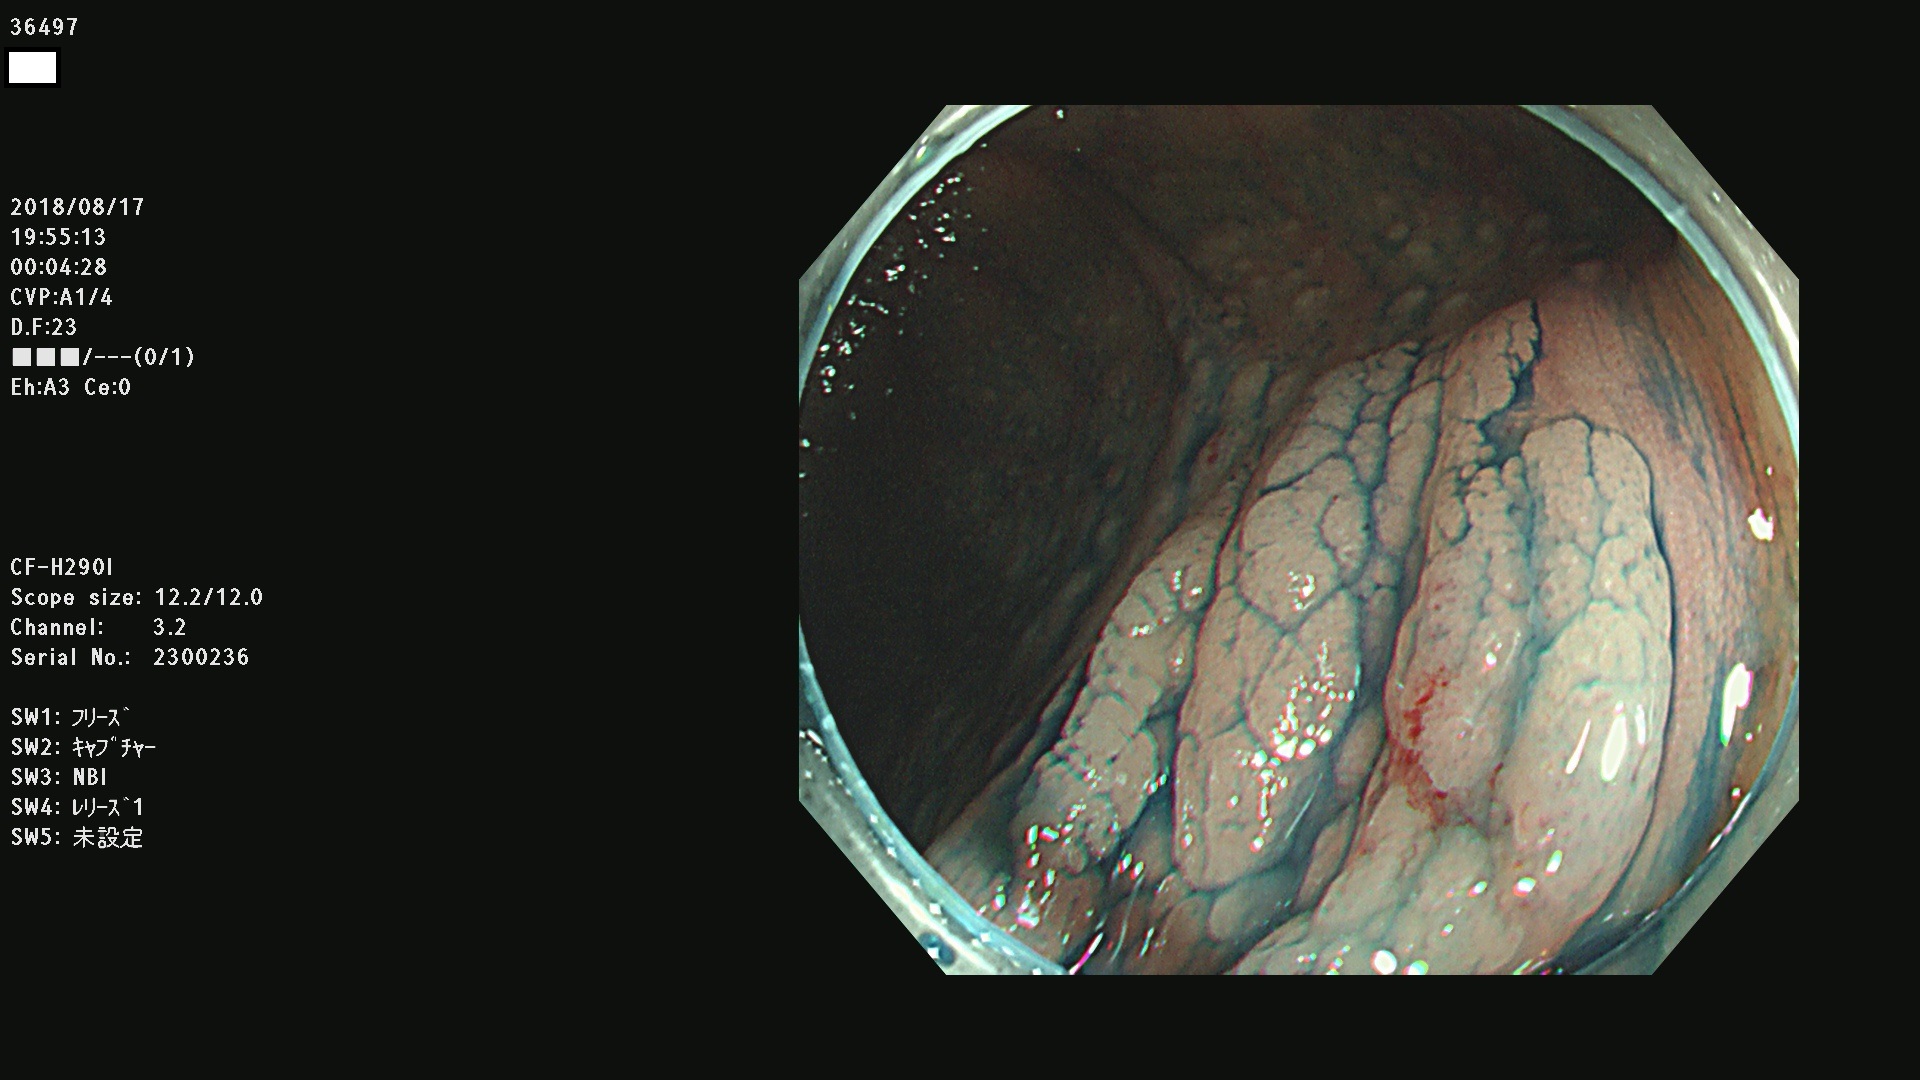

36400(SSAPのみ) 36402 36403 36404 36405 36406 36407 36408(SSAPのみ) 36412 36413 36414 36415 36416 36417 36418 36420 36422 36423 36424 36425 36426 36428 36429 36430 36431 36434 36435 36436 36437 36438 36440 36443 36447 36448 36449 36450 36452 36454 36458 36459 36460 36462(SSAPのみ) 36463 36464 36465 36466 36470 36471 36472 36473 36474 36475 36476 36478 36480 36481 36482 36484 36487 36488 36489 36490 36492 36494 36495 36496 36497 36498

発見困難で危険性の高い平坦型病変(上記100名より抽出)